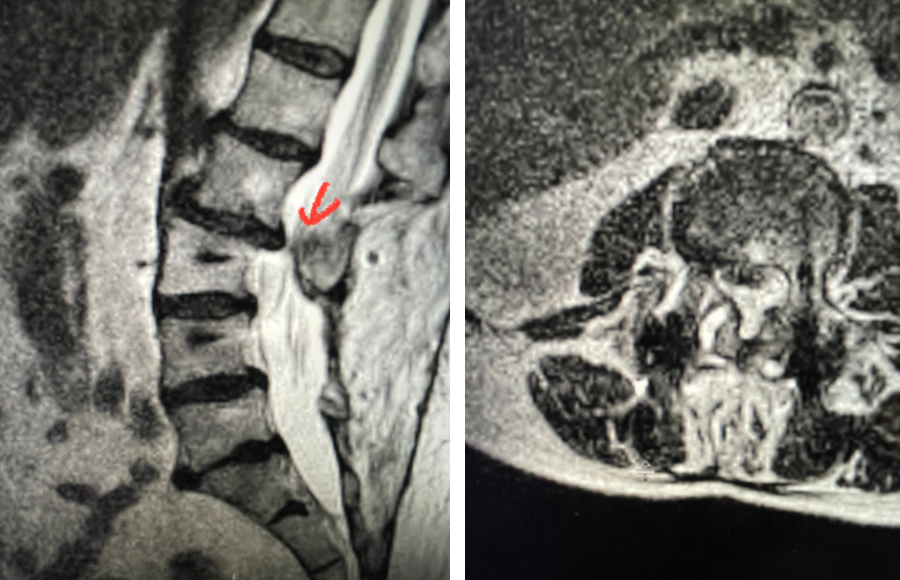

Another interesting 54-year-old patient presented with low back pain and severe left lower extremity pain over two months. He had a history of falls. The pain in the leg was more bothersome to the patient. The patient had a work-up with an MRI and CT of the lumbar spine. MRI demonstrated a subtle grade 1 spondylolisthesis L5-S1 with a dysmorphic L5 vertebral body (Fig 2). There was a suggestion of a left L5 spondylolysis or defect in the bridge of bone that connects the superior facet process of the segment and the inferior facet process. A CT of the lumbar confirmed this unilateral abnormality which certainly could account for the patient’s left leg pain (Fig 3). This is an unusual finding in that most patients have bilateral pars defects. Patients with L5-S1 often have congenital abnormalities of the lumbosacral junction including weird shaped, elongated or dysplastic facet joints. A subtle L5-S1 spondylolisthesis with an associated smaller and misshapen L5 vertebral body is often associated with L5 spondylolysis. In addition, with a dysmorphic L5 vertebral body, there is secondary disc degeneration at L5-S1 and sometimes at the L4-5 disc with an associated retrolisthesis at L4-5. There is less surface to surface contact of the L4-5 and L5-S1 leading to chronic segmental instability.

Fig 4: Sagittal and axial T2-weighted lumbar MRI images demonstrating severe next segment degeneration and stenosis at L2-3 above prior L3-5 fusion. Note retrolisthesis and significant facet arthropathy at L2-3 (red arrow).